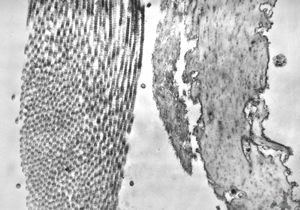

F, 39y. | collagenous and elastin fibers from corium

F,68y. | collagenous and elastin fibers from corium